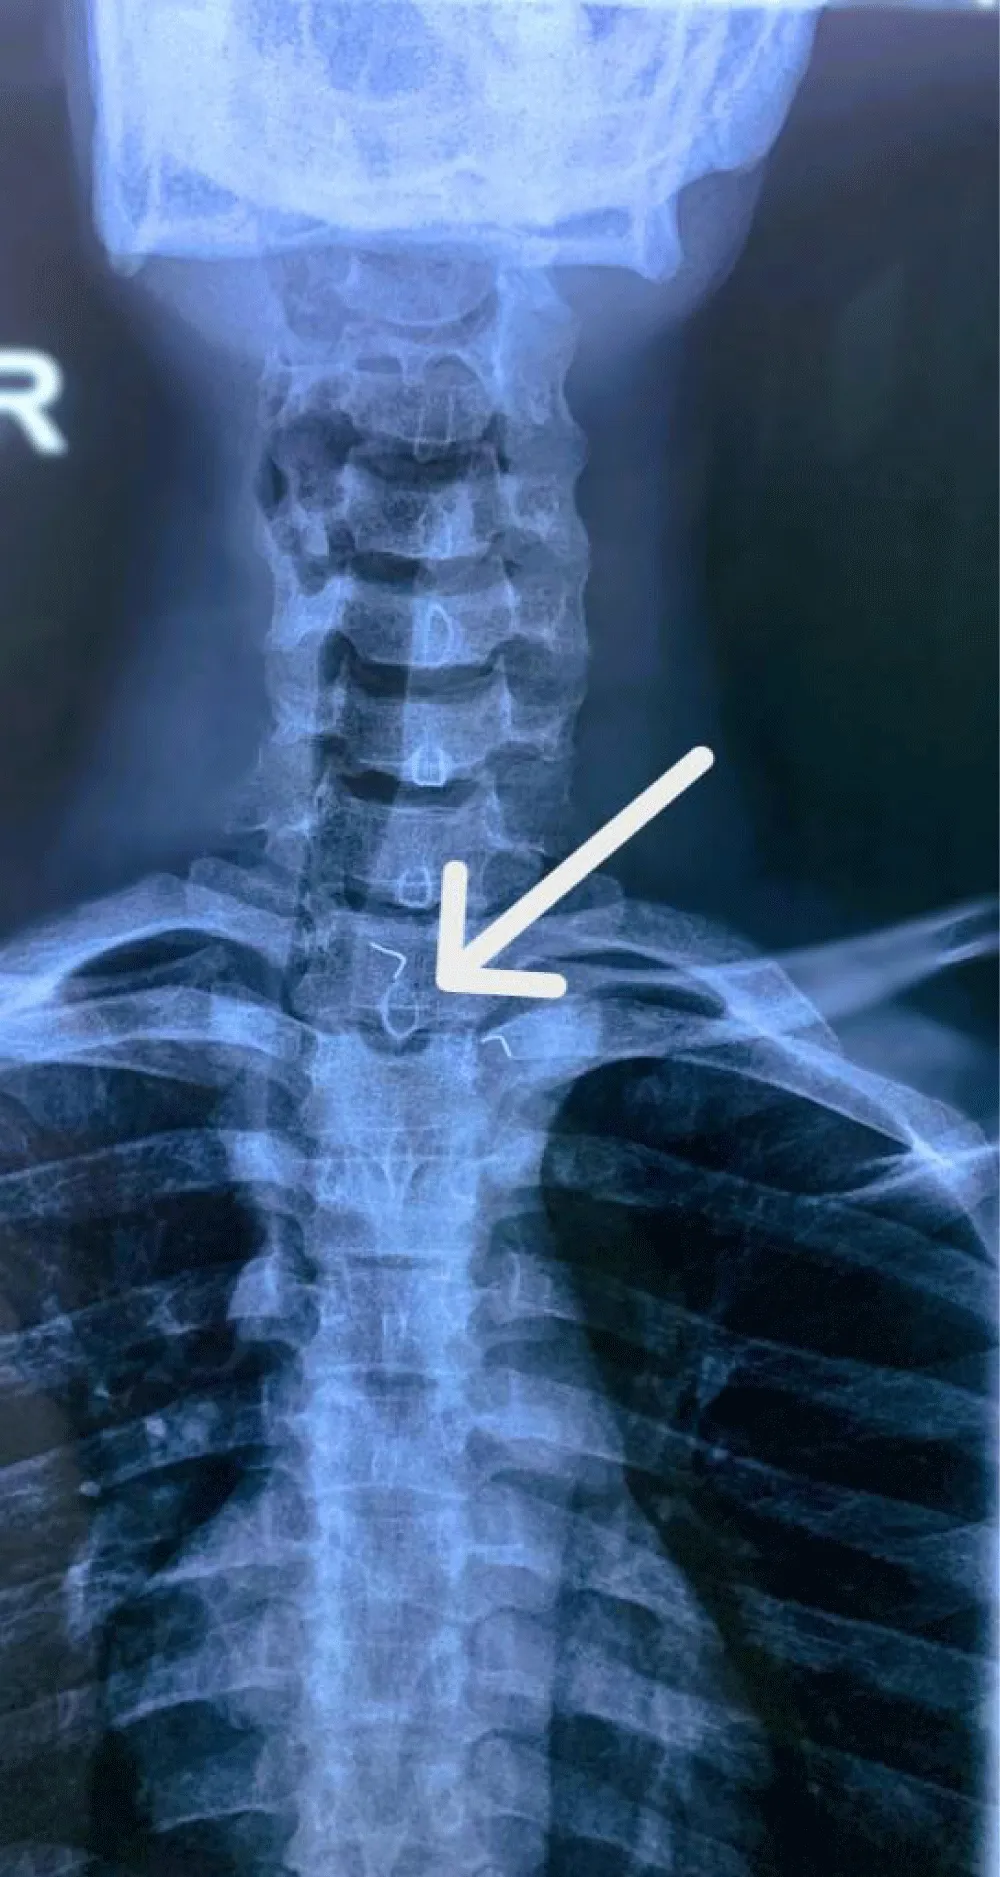

A standard chest X-ray revealed a metallic-looking image resembling denture clasps in the cervical esophagus at C5 (Figure 1).

A standard chest X-ray revealed a metallic-looking image at the cervical esophagus at C5, resembling the clasps of a denture.